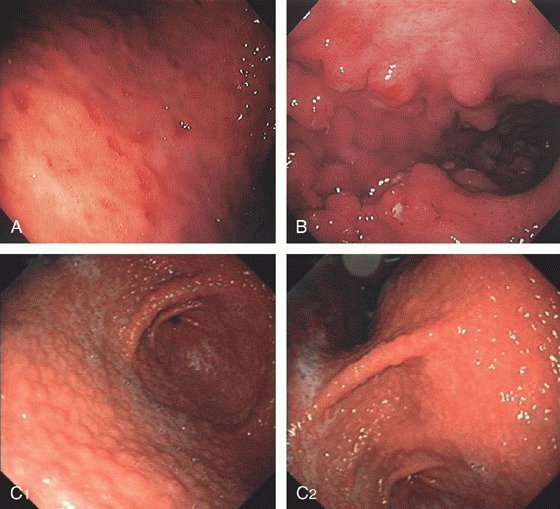

Эритематозная форма гастрита относится к достаточно распространенным ЖКТ патологиям, при которых на желудочной слизистой образуются характерные эритематозные пятна, со временем переходящие в эрозивные образования.

Подобные пятна имеют овальную форму, а по цвету могут быть ярко-красными или розовыми. Данная гастритная форма относится к хроническим воспалительным патологиям, при которых поражения распространяются только на поверхностные слизистые оболочки. Кроме того, патология обычно локализуется в антральной части органа.

- ФГДС – «золотой стандарт» диагностики, методика, позволяющая обнаружить воспалительные изменения слизистой, в том числе и эритематозный гастрит с тотальным поражением желудка (пангастрит он же).